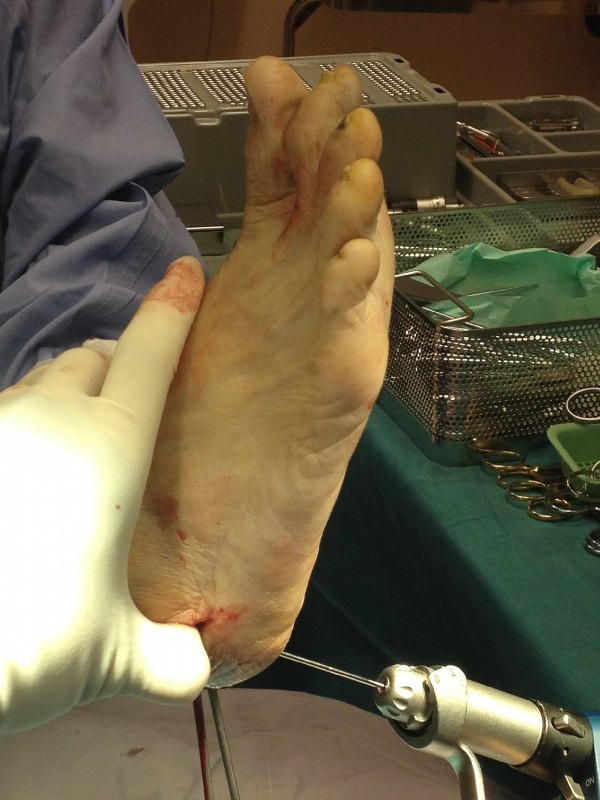

This is a 60 year old lady with painful right adult acquired flat foot.

She has collapse of the medial arch with heel pointing outwards (heel valgus). The posterior tibial tendon was stretched, painful but intact.

The deformity was still passively correctable.

I performed a tendon transfer – Flexor Digitorum Longus (FDL) transfer as well as a medial calcaneal osteotomy.

Note the correction of the right heel valgus into neutral.